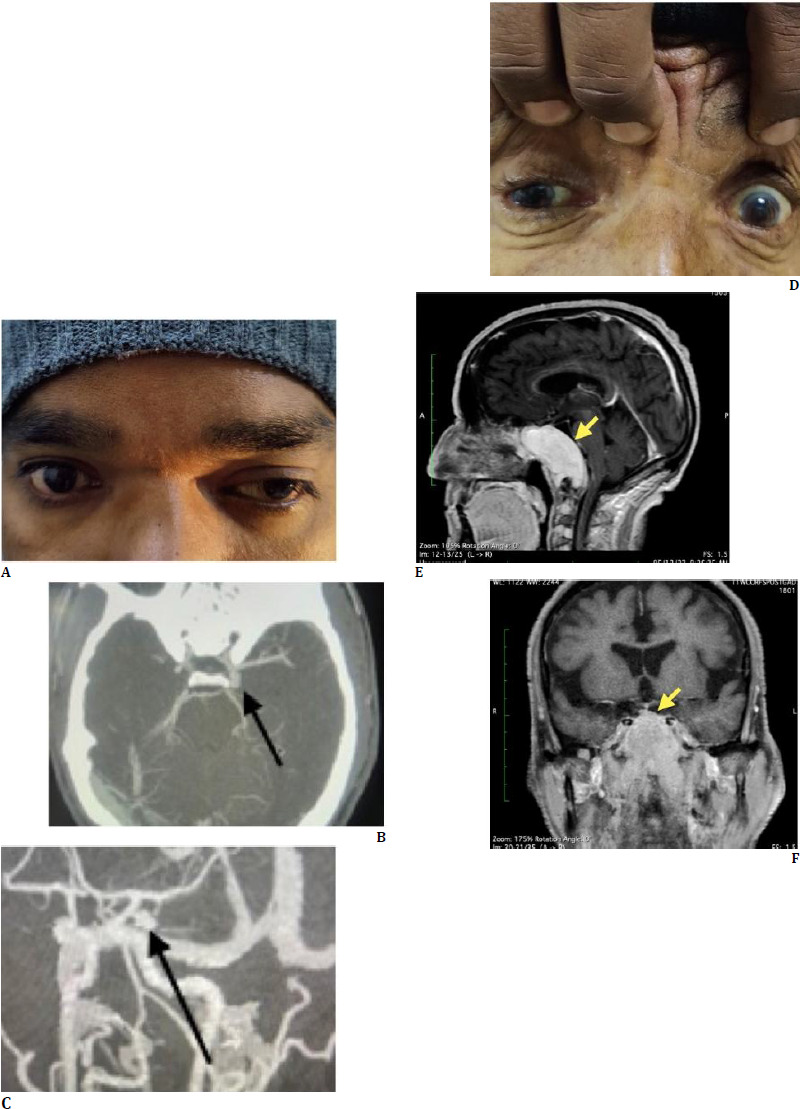

Case series: In the first case, a 36-year-old man came in with a left-sided headache and isolated third nerve palsy. Detailed investigations led to the discovery of a supraclinoid internal carotid artery aneurysm, necessitating prompt neurosurgical intervention. The second case featured a 74-year-old man with complete drooping of his right eyelid. The diagnosis of complete third nerve palsy led to further tests, which uncovered multiple myeloma. The third case involved a 19-year-old girl who had persistent double vision and bilateral ptosis. A collaborative effort between ophthalmologists and neurologists revealed Miller Fisher syndrome, which was successfully treated with intravenous immunoglobulins. Lastly, the fourth case described an 8-year-old girl who presented with optic neuritis. A thorough ophthalmological evaluation led to the diagnosis of Neuromyelitis Optica Spectrum Disorder, enabling early treatment and significant improvement.